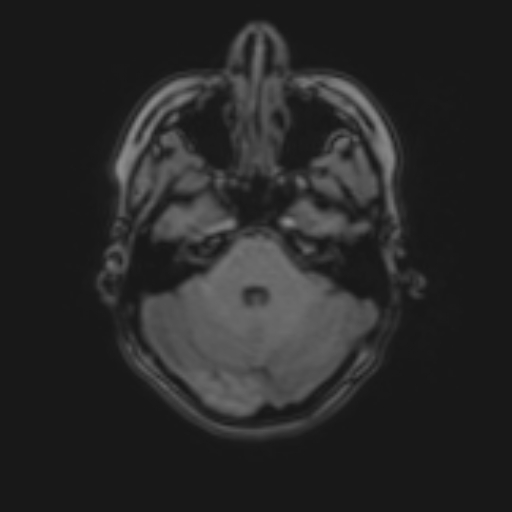

Nome Paziente: MACARI^NATALIA Identificativo: VSM_01222260 Data di Nascita: 07-06-1995 Sesso: F

Esame: RM ENCEFALO MDC del 24-03-2026